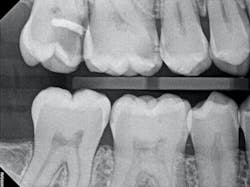

In the case below, tooth No. 2 was diagnosed with symptomatic irreversible pulpitis and symptomatic apical periodontitis with a mesial marginal ridge fracture due to extensive caries (figure 1). Root canal therapy and a full coverage crown were recommended and the patient accepted.

The carious tissue was removed, followed by the endodontic procedure and subsequent placement of the build-up. Despite the deep extent of mesial decay, a clear and accurate scan was achieved (figure 2).

The iTero scanner was able to clearly define the delineation between the soft and hard tissue as can be seen in this image of the digital die trim (figure 3). Radiographs were captured on delivery revealing a clinically acceptable outcome for the patient (figure 4). Direct restorations were completed on teeth Nos. 3 and 4 during this visit.